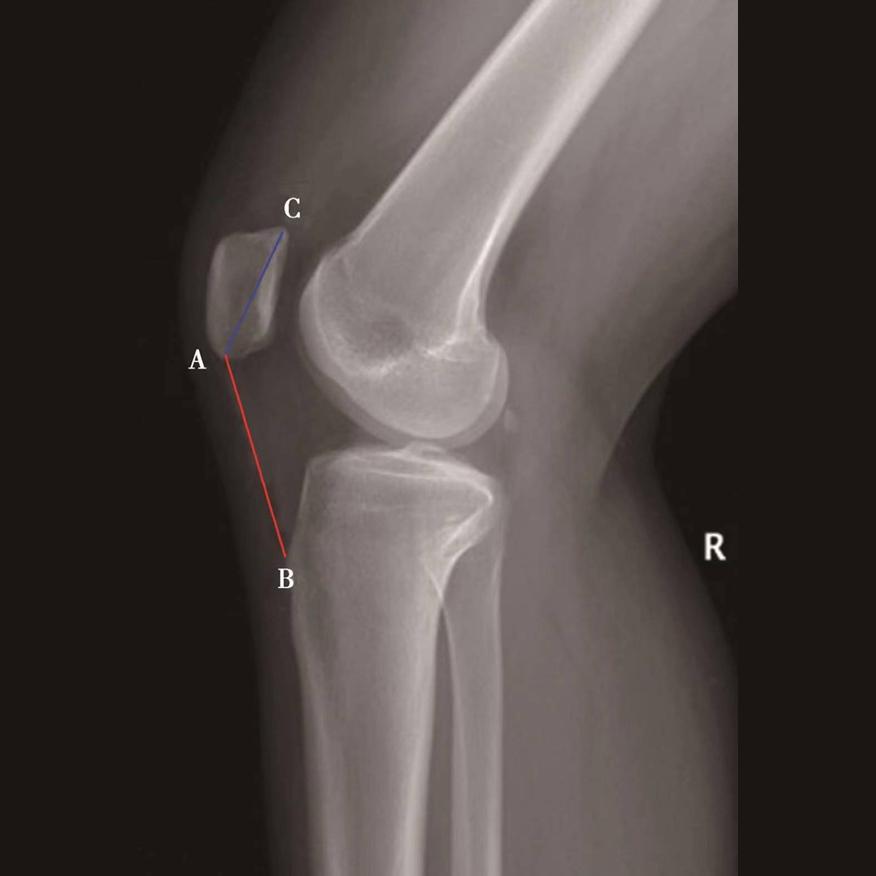

如图示:AB为髌骨关节面最低点到胫骨平台轮廓前上角最短的距离,AC是髌骨关节面的长度。Caton指数=AB/AC(图1)。

图1

图2 Caton指数=AB/AC=1.10,为正常髌骨高度

临床工作中常常使用其来估计胫骨结节移位的效果。正常人的Caton指数=1,正常范围0.8~1.2(图2)。需要注意的是:术前规划胫骨结节需要移位的理论距离为AB-AC,这就是需要将胫骨结节向远端移位的最大距离。但在术中胫骨结节转移的距离往往要小于这个距离,避免因过度移位造成医源性的低位髌骨。